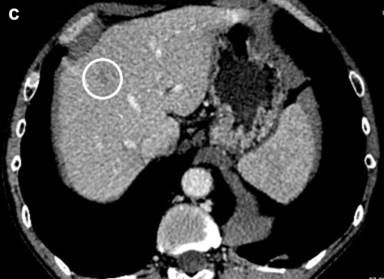

Figure 2. a. The contrast enhanced CT revealed newly found liver metastases (marked) suggestive of disease progression. b. The contrast enhanced CT image before HIFU showed a hypodense lesion of a liver metastasis about 14 mm in diameter in the right lobe (segment seven). c. Twelve months after the combination treatment with HIFU and chemotherapy the liver metastases were significantly reduced on the contrast control CT. |

Twelve months after the HIFU ablation, CT revealed a decreased tumor size to 18 mm (Figure 6). An objective anatomical landmark, confirming the shrinkage of the formation during the patient follow-up was the distance between the aorta and the superior mesenteric artery. Before HIFU ablation the distance was 8.2 mm, and 12 months later it reached 23 mm (Figures 3 and 6). The control CT also showed remarkable reduction of the liver metastases (Figure 2c). The quality of life evaluated by the same EORTC instruments remained stable.